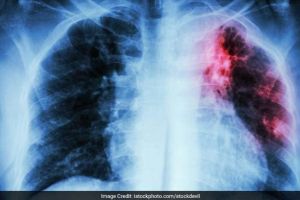

Tuberculoza Pulmonară: Simptome, factori de risc, tratament şi prevenţie

Tuberculoza (TBC) este o boală infecto-contagioasă larg răspândită în întreaga lume, cauzată de bacteria Mycobacterium tuberculosis. Este una dintre cele mai frecvente boli infecţioase din lume, de aceea e considerată o problemă de sănătate publică, diagnosticul şi tratamentul fiind gratuite în România. Infecţia se răspândeşte prin calea aeriană. Acest tip de transmisie înseamnă că, atunci …